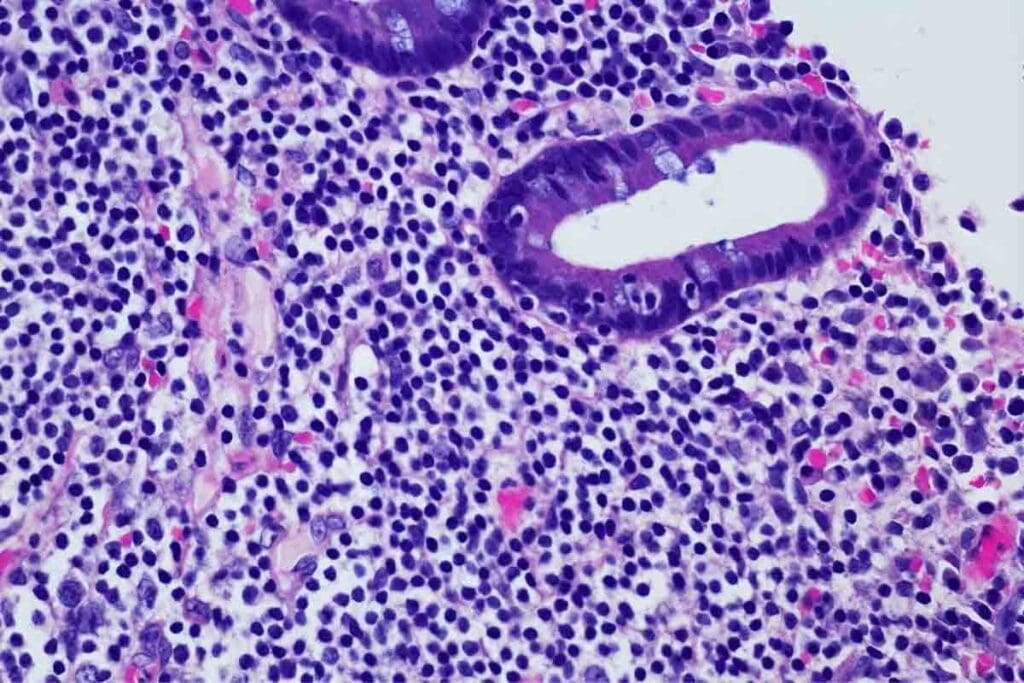

Bone Marrow Biopsy and Cellular Analysis

A bone marrow biopsy is a key test for ALL. It takes a bone marrow sample, usually from the hip, to look at cells under a microscope. This helps find leukemia cells and learn about them.